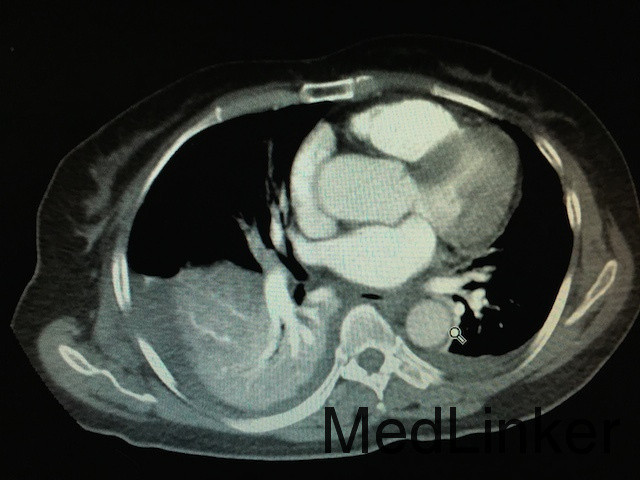

随访:患者病情稳定后行胸部CTA如下图:双肺动脉分支栓塞,双肺片状影,双肺下叶局部膨胀不全,双侧胸腔积液。转至ICU后,患者生命体征稳定,暂不考虑行溶栓治疗,予以低分子肝素继续抗凝治疗,复查ECG后示:Q波深度较浅减低,T波恢复正常,抗凝有效。 讨论:患者为PCNL术后,由于手术时间长,且术中由于行结石位,下肢长时间受压,加上患者年龄大,很容易形成深静脉血栓,患者下地导致血栓脱落,阻塞肺部血管,造成肺动脉栓塞。